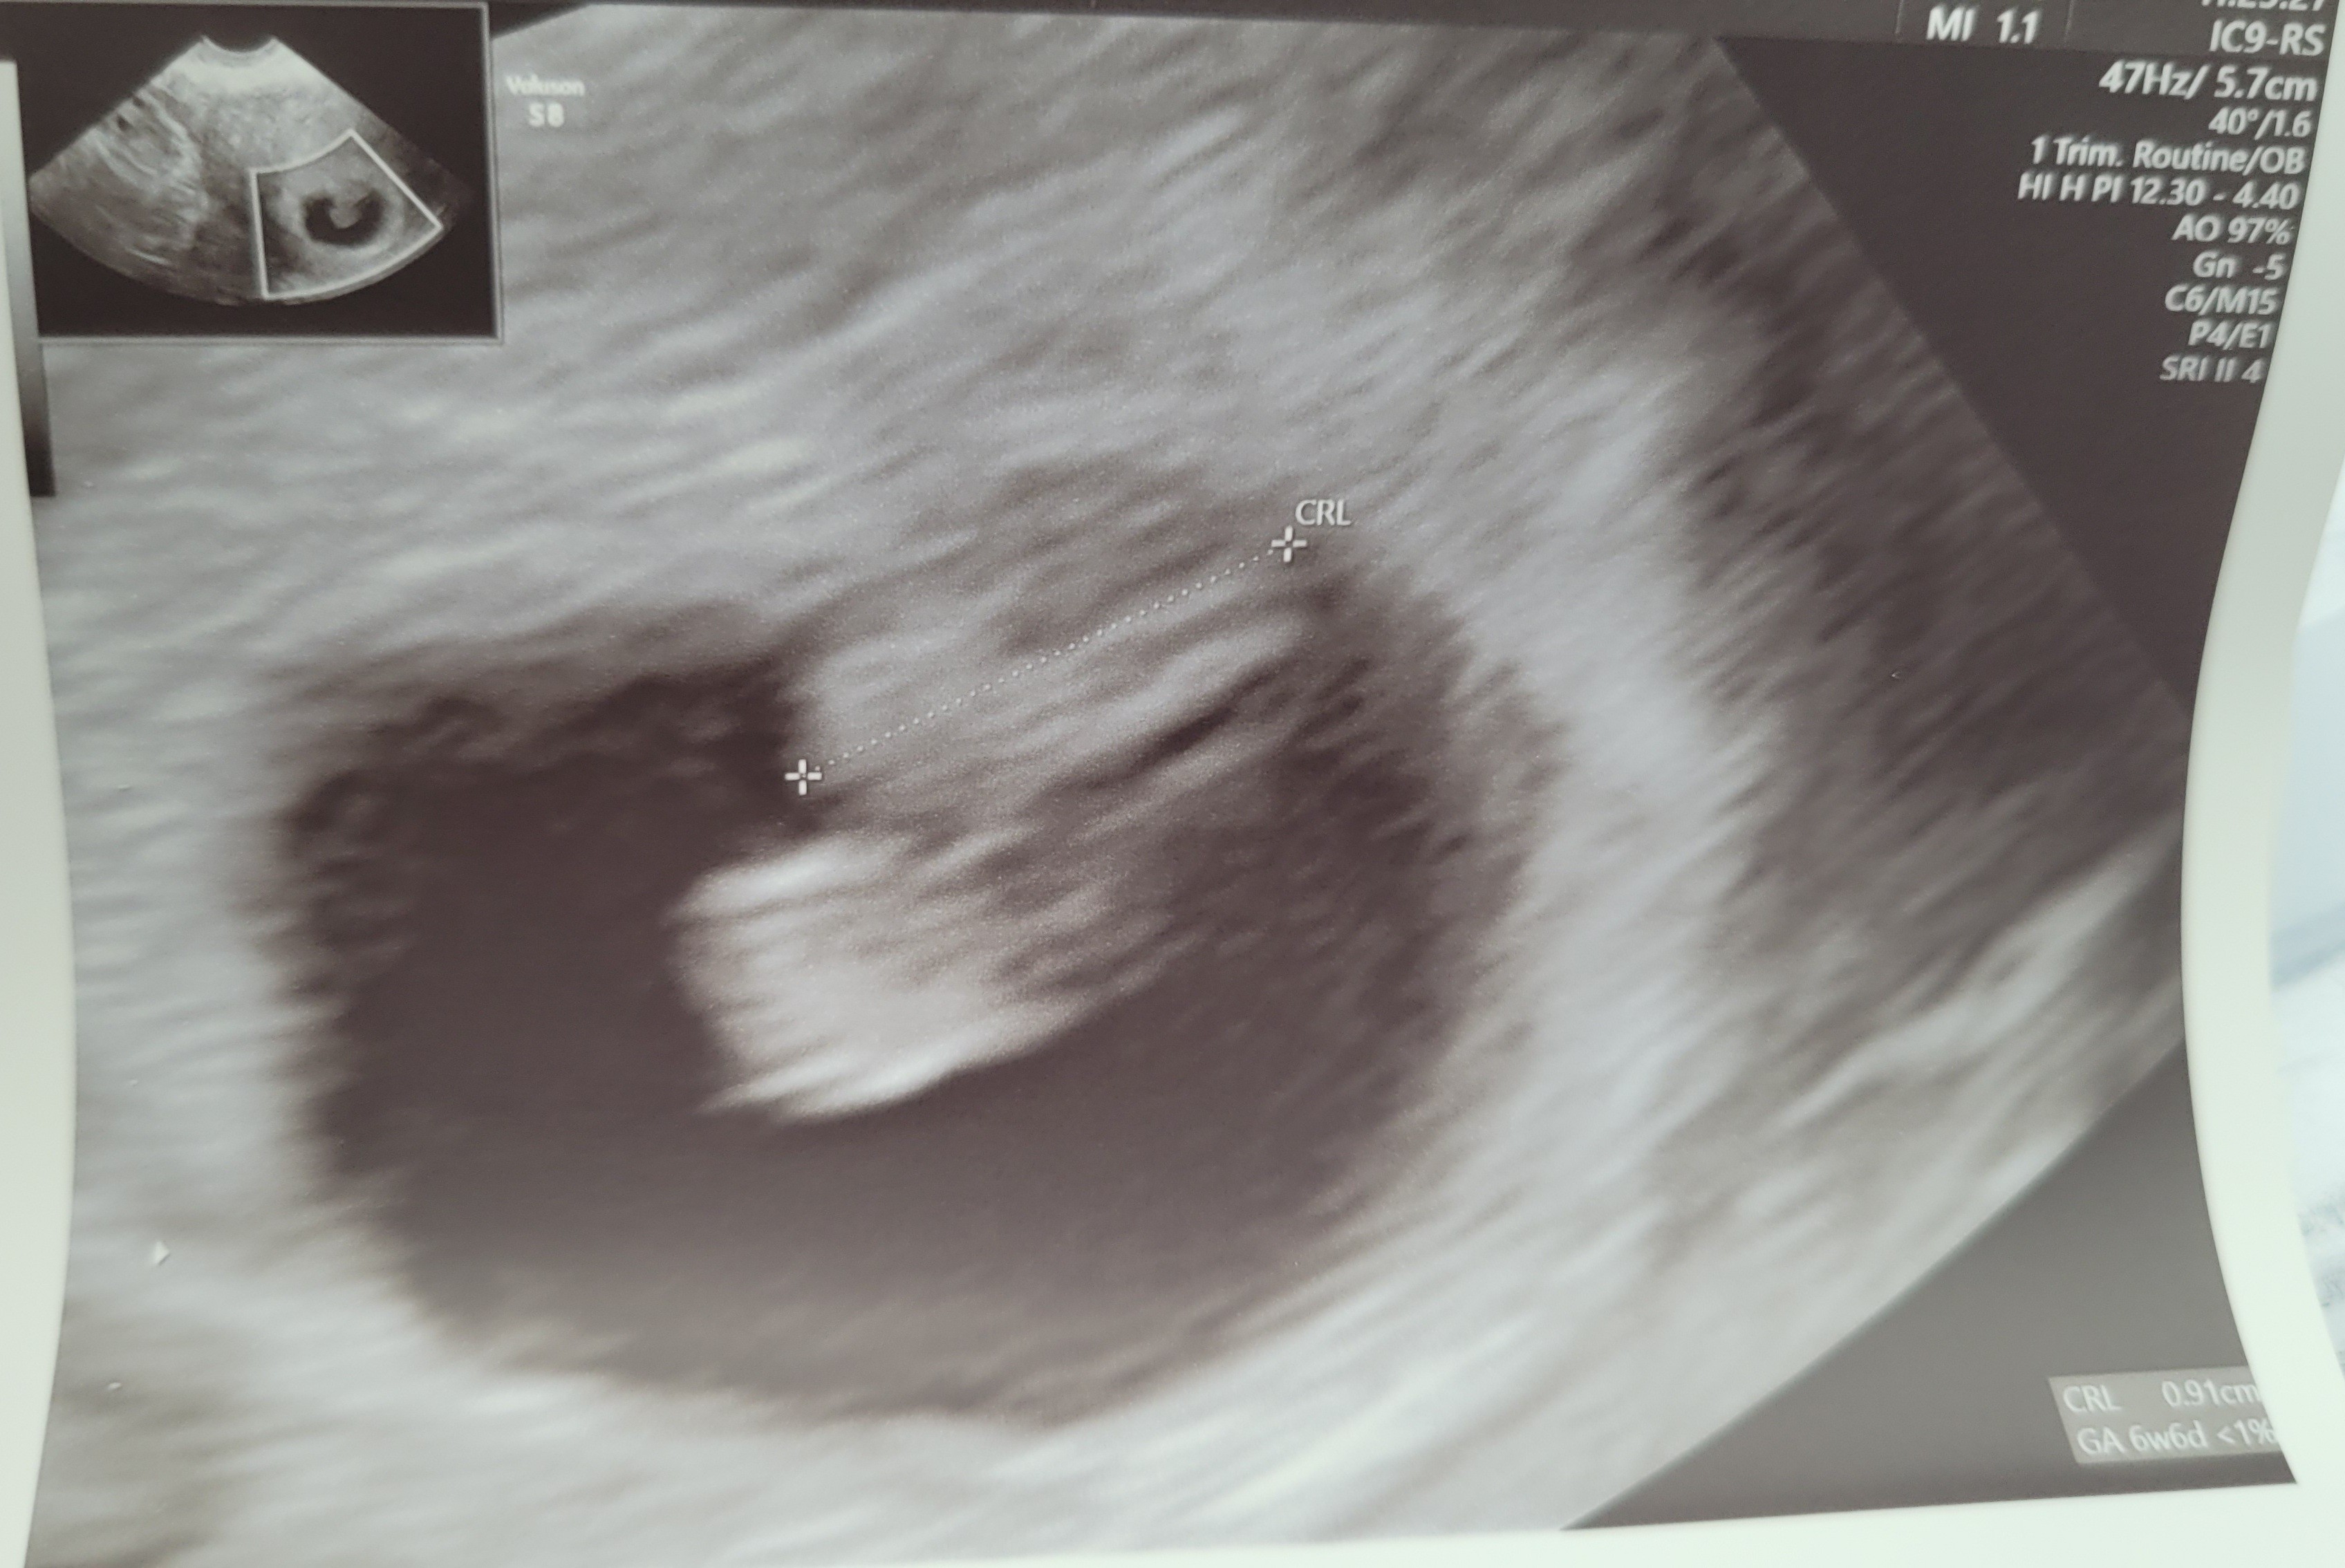

Dziewczyny przedstawiam mojego Smoka 🥰😍 tydzień ciąży 7+0, karta ciąży założona , serduszko pięknie bije. Jestem taka szczęśliwa 🤩

Załączniki

• 20210720_114723.jpg